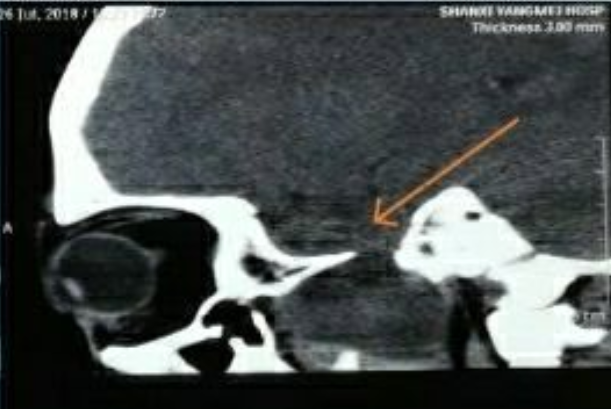

术前CT显示肿瘤和扩大的卵圆孔